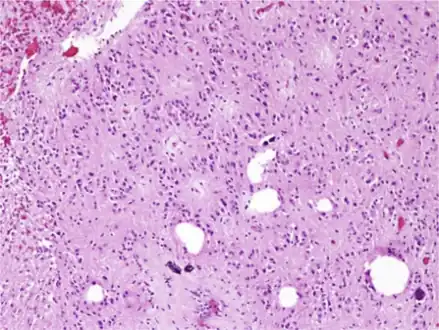

| Micrograph of a subependymoma showing the characteristic clustering of nuclei. H&E stain. | |

Characteristic clusters of nuclei in a dense fibrillary background suggestive of subependymoma

The diagnosis is based on tissue, e.g. a biopsy. Histologically subependymomas consistent of microcystic spaces and bland appearing cells without appreciable nuclear atypia or mitoses. The nuclei tend to form clusters.